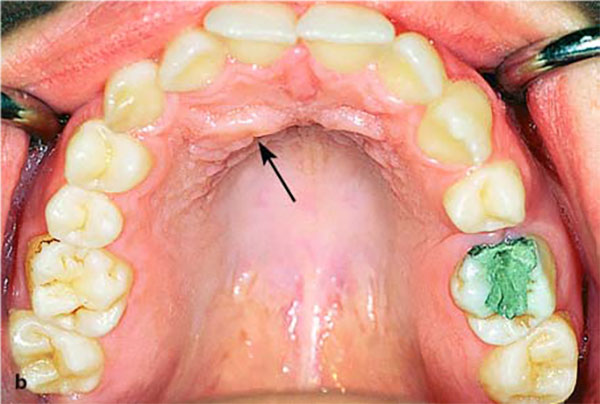

معمولا افرادی که با نهفتگی دندان نیش مراجعه میکنند یک دندان نیش شیری در دهان دارند که به دنبال پوسیدگی دندان شیری و برای جایگزینی آن دندان شیری مراجعه نمودهاند و متوجه وجود نیش نهفته میشوند. سناریوی دیگر این است که به دنبال وجود برجستگی در کام یا لب به مطب ها مراجعه می کنند. و یا اینکه والدین و یا دندانپزشک کودک متوجه عدم رویش دندان نیش دائمی شده و بیمار را جهت درمان به متخصص جراح فک و یا ارتودنسی ارجاع می دهند. متخصصین ارتودنسی معمولا توصیه می کنند تا کودکان را در سن ۷ سالگی برای رادیوگرافی کلی جهت بررسی روند رشد دندانها و ناهنجاری ها نزد پزشک ببرند. عمدتا، اصلی ترین دلیل رشد دندان نهفته نبود فضای کافی در فکین است برای باز کردن فضای فکین می توان به ارتودنتیست مراجعه نمود تا از دستگاه اکسپندر یا بازکننده کام برای رفع این مشکل استفاده نماید.عوامل موثر در درمان نیش نهفته

عواملی که بر درمان نیش نهفته تاثیر می گذارند عبارتند از: سن بیمار، محل نهفتگی (لبیال یا پالاتال)، زاویه و عمق نهفتگی، میزان فضای قوس دندانی و … از جمله درمانهای شایع برای هدایت نهفتگی به داخل قوس دندانی میتوان به مواردی اشاره کرد مانند کشیدن دندان نیش شیری، باز کردن فضای رویش نهفتگی با ارتودنسی اکسپوژر جراحی تاج دندان نهفته و هدایت آن به داخل قوس با نیروی ارتودنس.درمان نیش نهفته با ارتودنسی